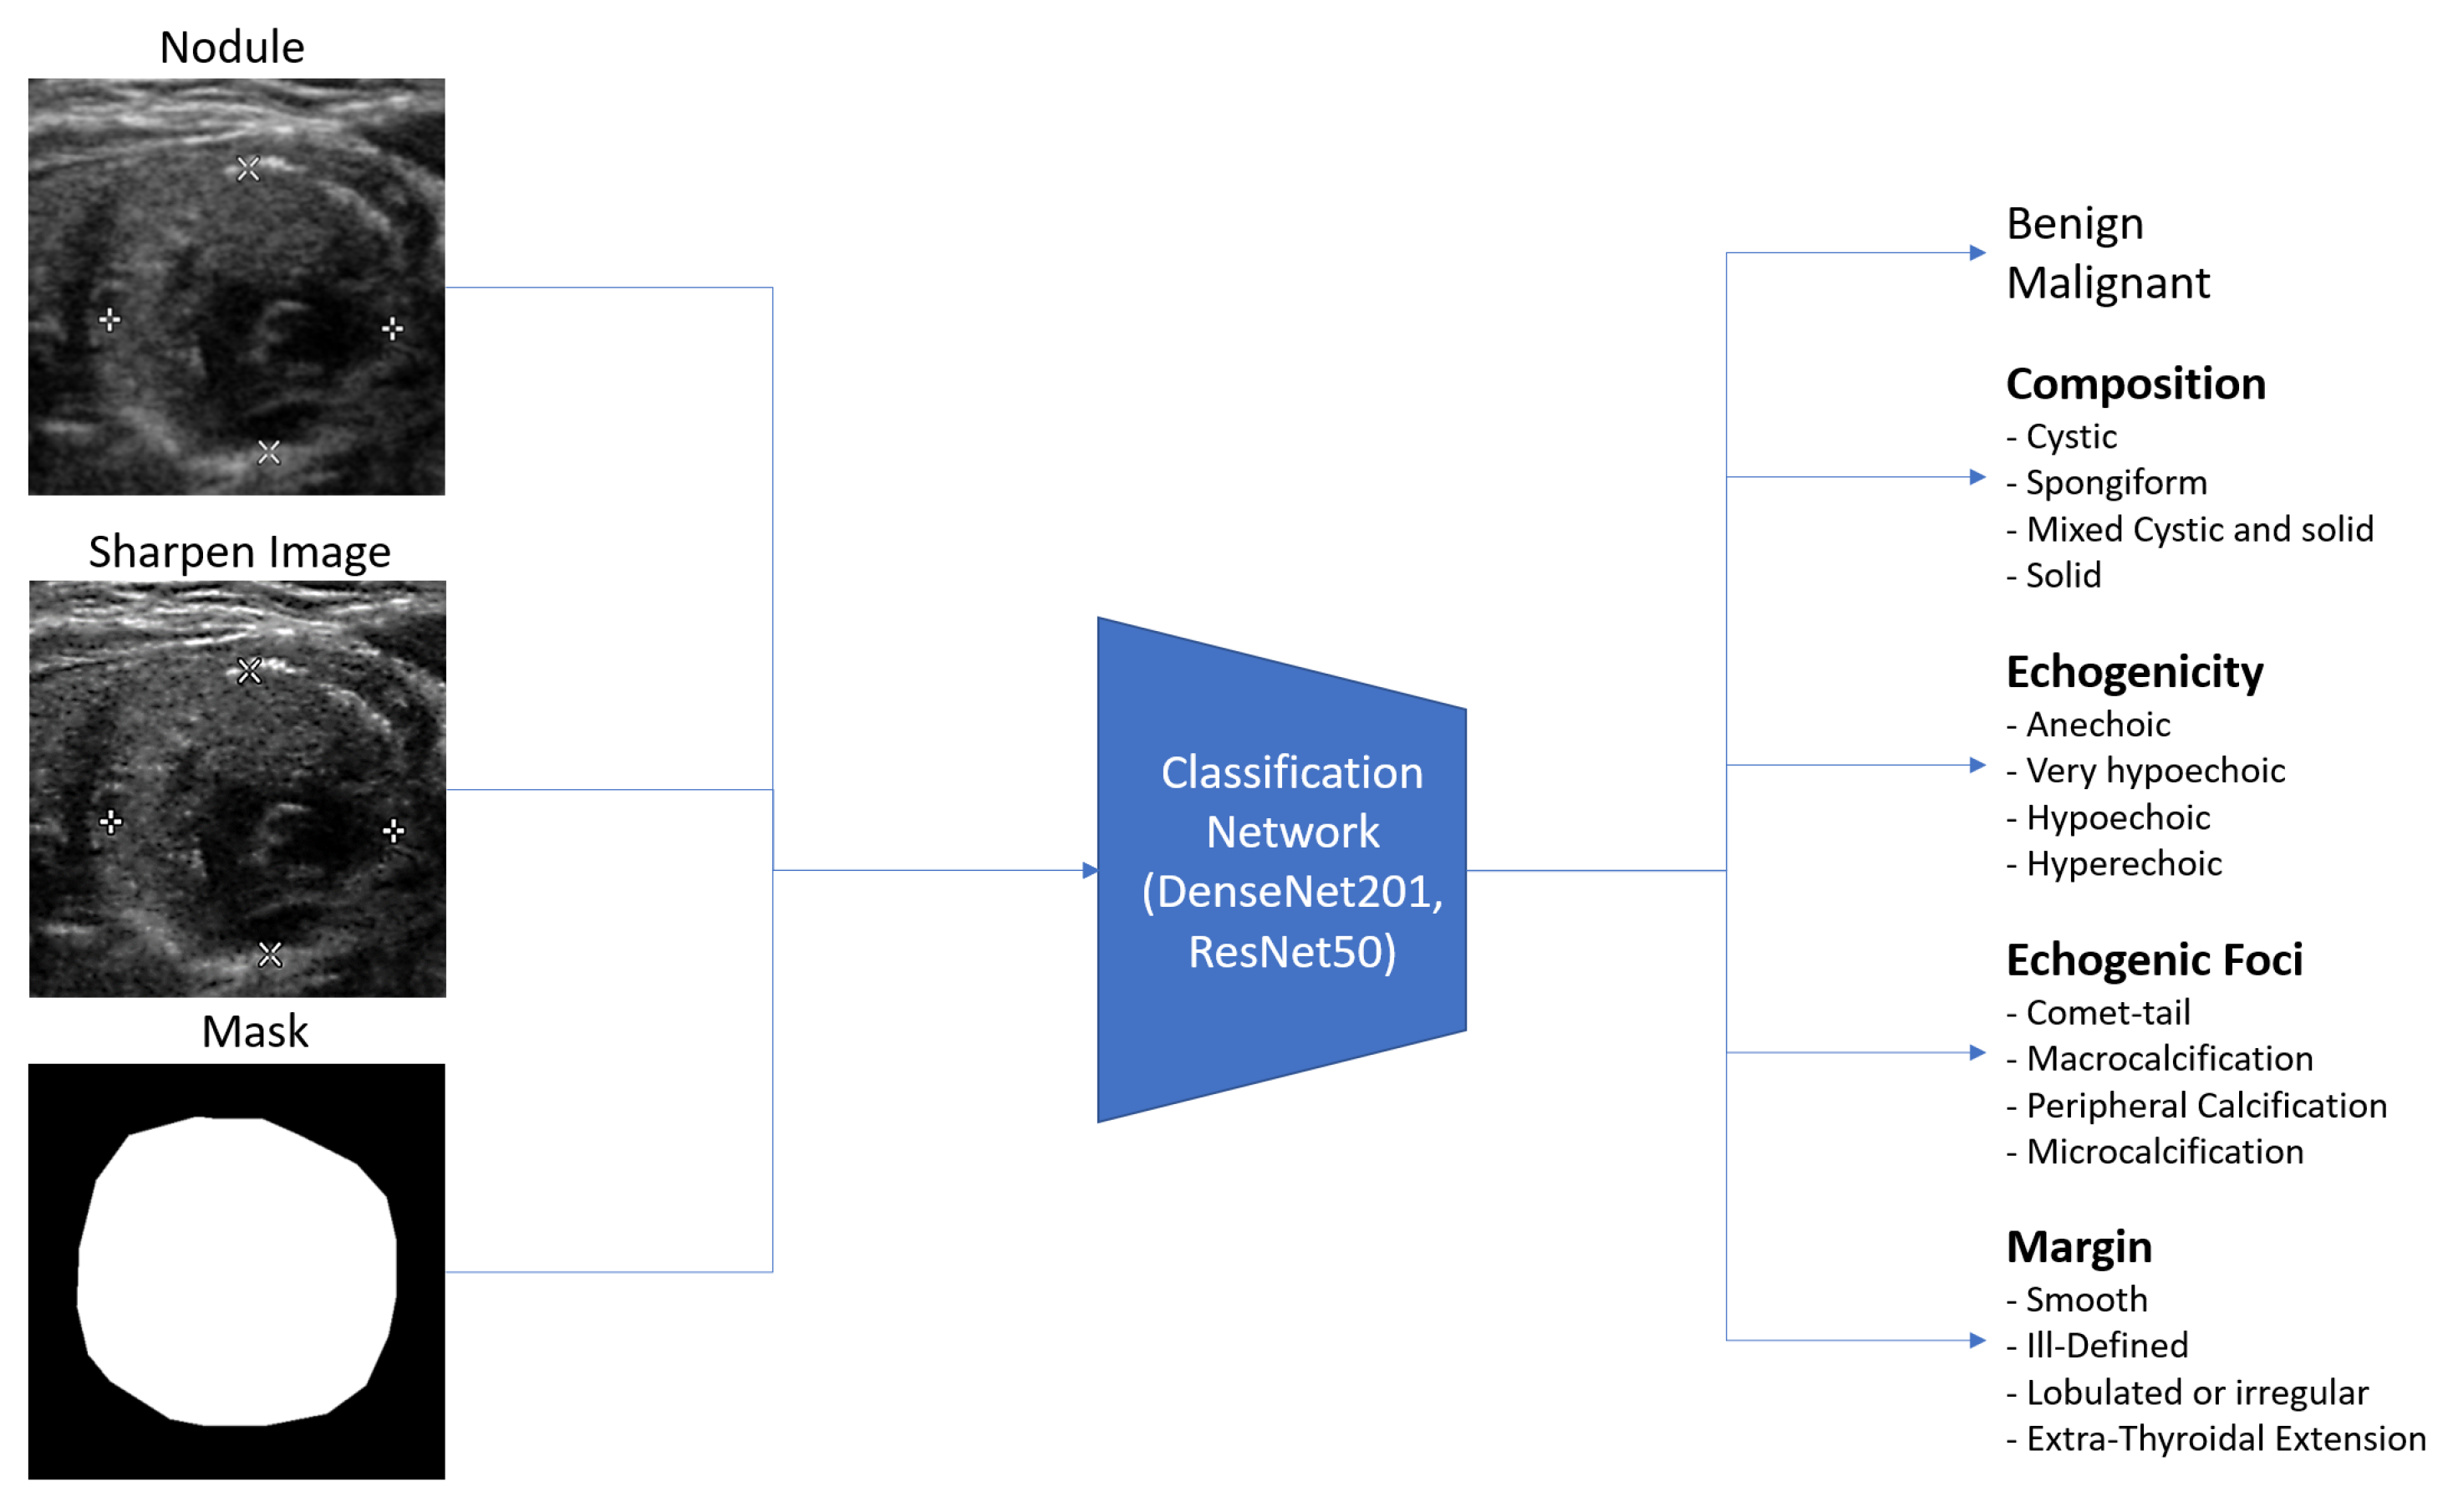

3.3. Input Images and Multiple Output Classification

Ultrasound images are typically grayscale, but they can be combined with other image types as input to a neural network. Multiple tensors of images can be used to convey different information, such as segmenting nodules to indicate their position. In this paper, we provide three tensors of images: an ultrasound image, a sharpened version of the ultrasound image (enhanced using 3 × 3 max-pooling with stride 1 to reveal micro-calcifications more clearly), and a segmented nodule image to concentrate the model on the nodule. The segmentation is implemented by StableSeg GANs [

24], as shown in detail in

Figure 5. Previous research has utilized ResNet and DenseNet to classify thyroid nodule ultrasound images as benign or malignant. However, no models have been designed for the multiple fine-grained classifications required by TI-RADS. To address this, we modified the ResNet50 and DenseNet201 classification models from a single output layer to multiple outputs, including TI-RADS types such as composition, echogenicity, margin, and echogenic foci. The model can easily calculate the shape of the nodule from the segmented nodule image, eliminating the need for the deep learning model to learn to predict the nodule’s size.

Figure 6 shows the overall input and output of the model.

Figure 6.

Overall input and output of the model, illustrating the integration of different image tensors and the multiple classification outputs for TI-RADS.

Figure 6.

Overall input and output of the model, illustrating the integration of different image tensors and the multiple classification outputs for TI-RADS.